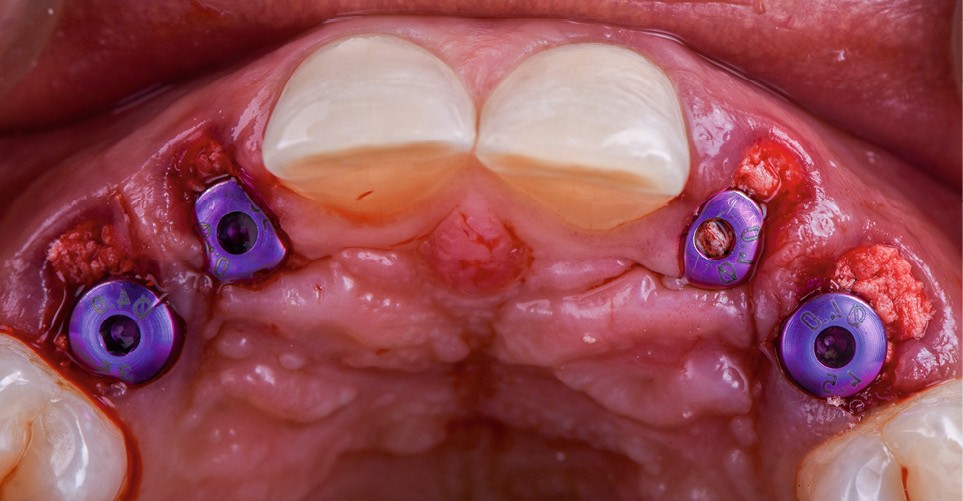

- extraction des dents 52 53 62 63 de manière « atraumatique » (fig. 3) ;

- installation du guide et forage implantaire à travers les canons de forage (fig. 4) ;

- mise en place de 4 implants Primetaper Dentsply (diamètre 3.6/ longueur 13 mm) ;

- vérification du positionnement implantaire et du torque à la clef dynamométrique : 45 Newton ;

- mise en place d’une vis de couverture sur les implants ;

- comblement du gap à l’aide d’un biomatériau combinant hydroxyapatite et trame collagénique (Ossix Bone Dentsply) ;

- dévissage des vis de couvertures ;

- mise en place des vis de cicatrisation (fig. 5) ;